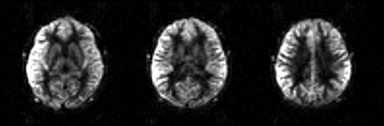

1.0 good image quality

- clean image with details in the grey matter

- symmetrical contrast between the left and right hemispheres

- good contrast between grey and white matter

- little signal or noise-like signal in the white matter